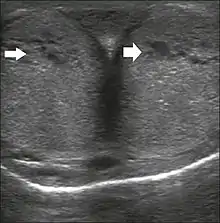

The corpora cavernosa are homogeneous and relatively hypoechoic cylindrical structures lined with tunica albuginea, a thin membrane that has a thickness of approximately 2 mm when the penis is flaccid and 0.25 mm when it is erect. The corpus spongiosum, a ventral, medial body that is more echoic than the corpora cavernosa, is also covered by the tunica albuginea and contains the urethra. As can be seen in Figures 1 and 2, it is more dilated and prominent in its proximal segment, known as the bulb, and in its distal segment, constituting the glans. Buck's fascia is superficial to the tunica albuginea and covers all of the structures described.[1]